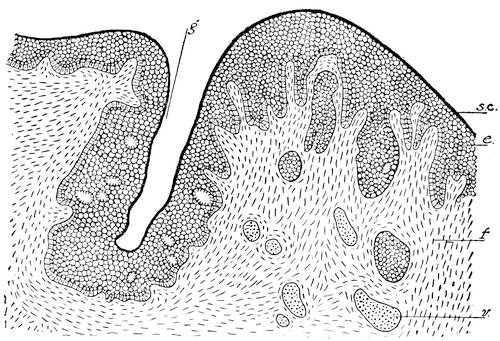

The scrotum being a derivative of the abdominal wall, it follows that its wall will consist of the same elements as the abdominal wall. The first layer of the abdominal wall, the epi30dermis or cutis, forms also the epidermis of the scrotum. The fascia superficialis abdominis constitutes the second layer of the scrotum, or the tunica dartos. The musculus obliquus abdominis externus goes to make up the third layer, the so-called Cooper’s fascia. The musculus obliquus abdominis internus forms the fourth layer, or the musculus cremaster externus. The musculus transversalis abdominis furnishes the cremaster internus muscle, and the tunica vaginalis communis, or the fifth layer. Finally, the double layer of the abdominal peritoneum forms the tunica vaginalis propria of the scrotum. Between the two lamina of this tunica is found some fluid which, when pathologically increased, constitutes the anomaly called hydrocele.